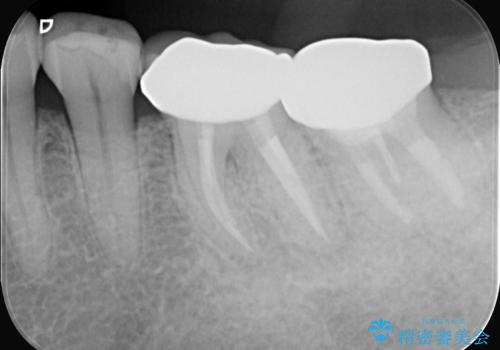

- 2日前から歯の痛みが続くという主訴でご来院されました。診察の結果、**不可逆性歯髄炎(歯の神経の重度の炎症)**と診断。レントゲンでは、歯髄腔が狭くなり、根管が石灰化している難症例であることが確認されました。患者様の大切な歯を残すため、歯科用顕微鏡を用いた精密根管治療を行うことで、狭く、見えにくい根管を正確に探し出し、治療を完了させる計画を立案しました。

今回の治療は、特に難易度の高い石灰化した根管が対象でした。まず、治療中の細菌感染を防ぐためにラバーダムを使用。次に、歯科用顕微鏡で治療部位を何十倍にも拡大しながら、狭窄した根管の入り口を探し、慎重に拡大・清掃を行いました。顕微鏡を用いることで、肉眼では不可能だった根管内部の細かい構造を確認しながら、感染源を徹底的に除去することができました。これにより、難症例の奥歯でも再発リスクを抑えた適切な処置を行うことができ、治療後に痛みは解消。大切な歯を長期間にわたり保存することができました。